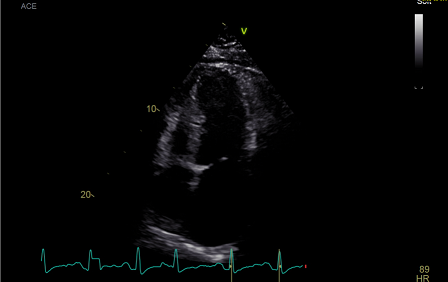

术前超声心动图

诊断:缩窄性心包炎、左室舒张功能减低、右室舒张功能减低。